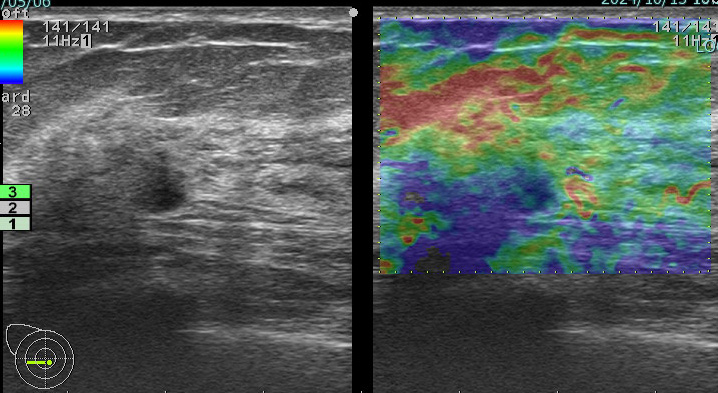

上に挙げた4つのエラストグラフィー

これが何を物語っているか?

エラストグラフィーは何か所見があった際に「これは怪しい!」と思わない限り追加で行わないものです。

これを実は4回も(昨年)行っていたのです。

つまり、(昨年も)その技師は「明らかに癌を疑っていた。」

この4枚のエラストグラフィーは技師の「これは怪しい所見です!是非要精査にしてください!」という心の叫びと言えるんだね!

まさに、その通り!

ただ、悲しいかな。技師さんのその「必死な思い」は、検診画像評価を行う医師には伝わらなかった。